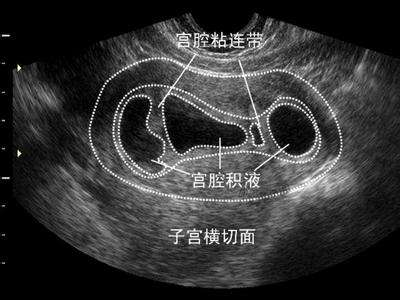

宫腔积液是指宫腔内积存的一定量液体,包括生理状态生殖道黏膜上皮细胞分泌的液体及病理状态的炎性分泌物、脓液和血性液体等。超声下往往显示宫腔内呈现无回声或者低回声区域,宫腔分离,内膜线消失。